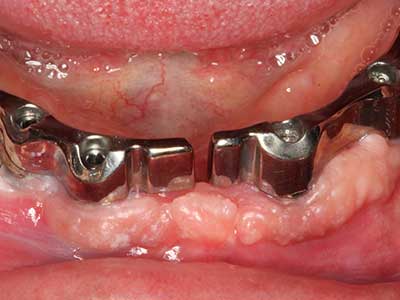

Indication: Periodontal therapy

Marginal periodontal diseases are the main reason for extractions in advanced age. These diseases are primarily caused by bacterial colonization of the gingival pocket, which causes inflammation followed by loss of the periodontium. The formation of subgingival biofilms and concrements is a significant aetiological factor for marginal bone atrophy, so their removal is an important part of the treatment (Drisko 2014, Plessas 2014).

Initial and surgical treatment phases are differentiated in the treatment of marginal periodontitis. In addition to instruction in oral hygiene and motivating patients, both phases should include adequate cleaning of the root surface. In the regenerative setting an open access is generally preferred. The root surface can be cleaned by piezosurgery using special attachments, where instruments with different curvatures are used to reach areas that are difficult to access, such as furcations. The integrated irrigation in the system flushes the detached concrements and bacteria out of the pocket. Specialized systems such as the Piezomed also include application feedback to minimize the ablation of hard dental substance. The greater the pressure on the periodontal attachment the greater the reduction in the amount of ablation.

Special soft tips for peri-implantitis therapy are opening up new prospects in dentistry. They are the subject of current research and initial results are very promising.